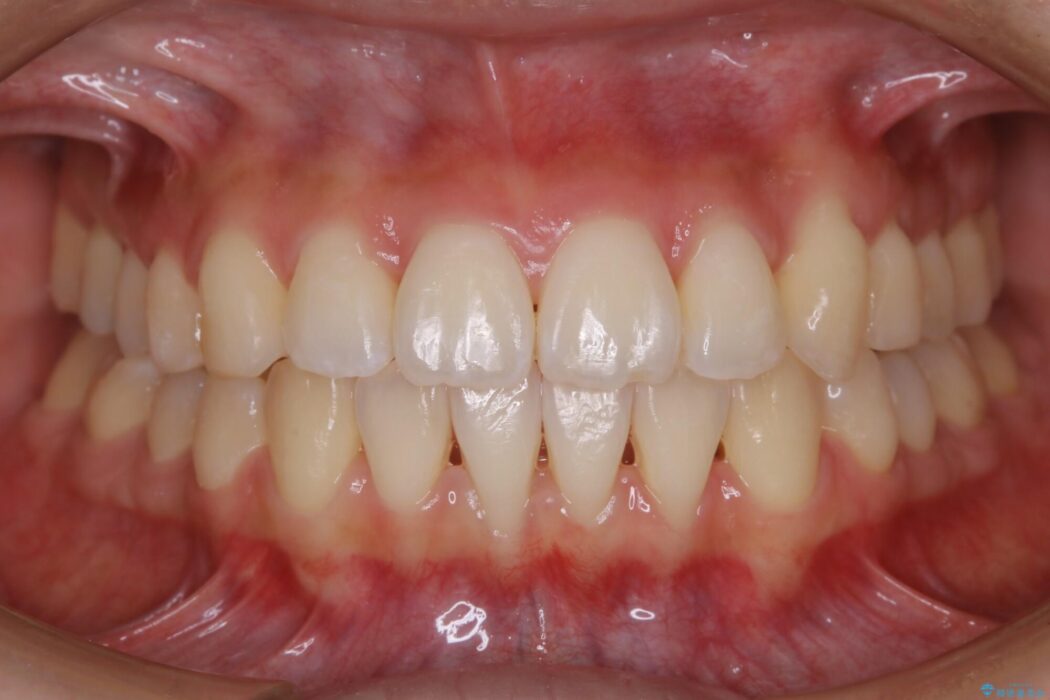

治療前と治療後を見比べると口元の見た目の変化が良く分かります。

本症例では奥歯から順に移動させるため前歯の変化を感じるには時間が掛かりましたが、インビザライン装置とマイクロインプラントを併用することで健康な歯を抜歯することなく歯列をきれいに整えることができました。